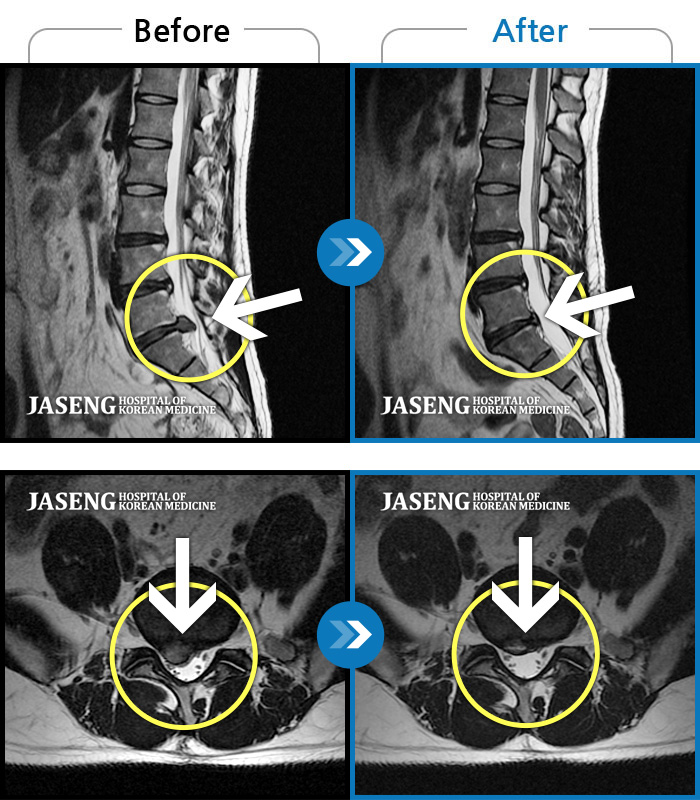

허리디스크

보라매 · 신원준 원장

좌측 허리부터 고관절 통증이 심하고 다리까지 저려서 허리를 똑바로 펴기 힘들어요.

촬영시기

2023.08.21 ~ 2023.11.20

2023.12.08